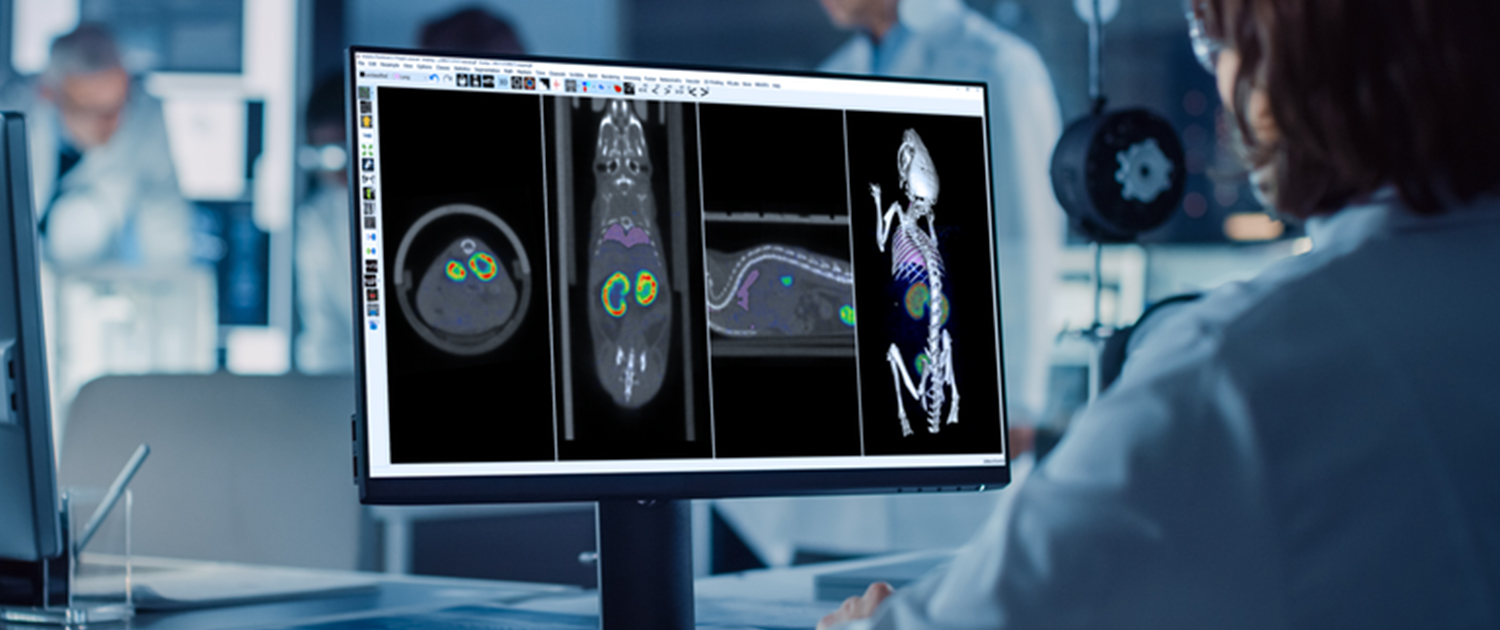

Image analysis is a critical component of clinical and preclinical imaging research, providing a means of quantifying and interpreting the data generated by imaging modalities such as PET, SPECT, and CT. In clinical imaging, image analysis is used to aid in diagnosis and treatment planning. For example, in oncology, image analysis can be used to assess the response to chemotherapy and radiation therapy, providing a means of monitoring the effectiveness of treatment and making adjustments as necessary.

In cardiology, image analysis can be used to evaluate blood flow and cardiac function, enabling the diagnosis and treatment of heart disease. In preclinical imaging research, image analysis plays a crucial role in the development of new treatments and therapies. Image analysis algorithms can be used to quantify the effects of drug treatments or surgical procedures on biological processes such as blood flow and metabolic activity. By providing a means of objectively assessing treatment efficacy, image analysis helps to optimize treatment protocols and improve patient outcomes.

At our company, we provide a wide range of image analysis services for both preclinical and clinical imaging research. Our team of experts has extensive experience in conducting image analysis for various modalities, including PET, SPECT, CT, and optical imaging. We offer a comprehensive set of services, such as image registration, segmentation, quantification, and statistical analysis. We understand the importance of accurate and precise image analysis in the success of research projects, and we use state-of-the-art software and techniques to deliver reliable and reproducible results.